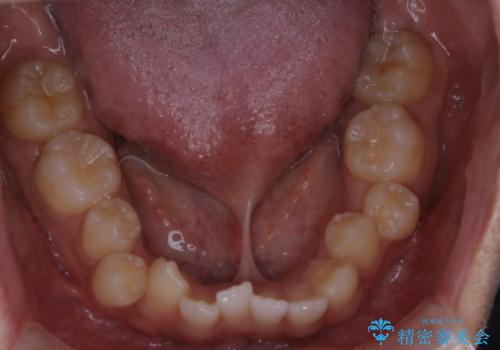

インビザライン単独でここまでできる!!抜歯矯正

- 治療計画

1日20時間以上、正しくインビザラインを使用して頂いたおかげで、ワイヤーに切り替えることなく矯正治療を終了することが出来ました。周囲からも歯並びがすごく綺麗になったと言われたのことで大変ご満足いただけました。